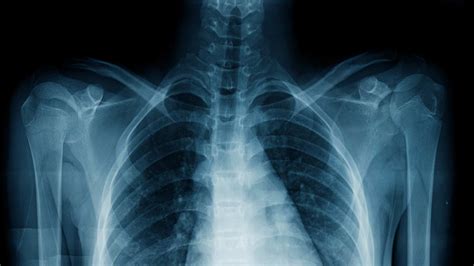

Sex X Ray technology involves the use of X-rays to produce images of the internal structures of the reproductive and sexual organs. This type of imaging is particularly useful for diagnosing conditions that affect the reproductive system, such as tumors, infections, and anatomical abnormalities. The technology works by passing X-rays through the body, which are then captured on a detector to create detailed images.

- Pelvic X-Ray: A general X-ray of the pelvic region that can help identify fractures, tumors, or other abnormalities in the bones and soft tissues.

- Digital Radiography: This technology uses digital detectors to capture images, providing higher resolution and faster processing times.

- 3D Imaging: Advanced Sex X Ray systems can produce 3D images, offering a more comprehensive view of the reproductive organs.